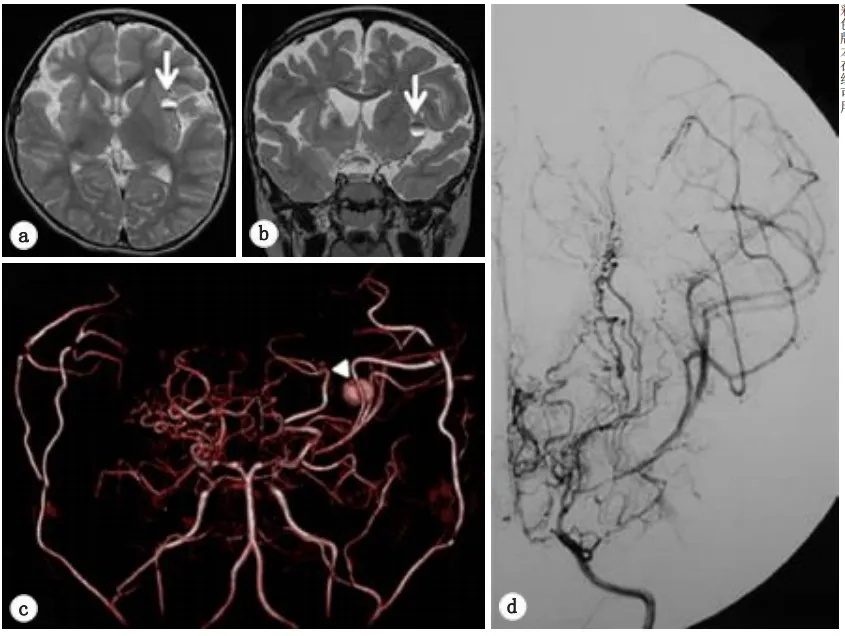

二次手术一年半后,在一次常规随访中,MRI发现左侧岛叶有一个小病变如图3a。复查脑MRA显示在左侧MCA远端有一个动脉瘤等圆形病变(图3b),然而,进一步的DSA检查排除了一个动脉瘤(图3c)。排除了脑内血肿或海绵状血管瘤等其他诊断病因可能,但由于桃子暂无无症状,暂时选择了保守治疗,包括减少阿司匹林剂量(2.5mg/5kg/天)。

图3.轴向(a)和冠状(b)T2加权磁共振图像显示左侧岛叶皮质有一个小的圆形混合强度质量(箭头)。c体积渲染磁共振血管造影。在大脑中动脉的左远端(箭头)发现一个浆果状病变,留下大动脉瘤的印象。d数字减影血管造影的动脉期。左侧颈内动脉造影术未发现动脉瘤等异常表现。